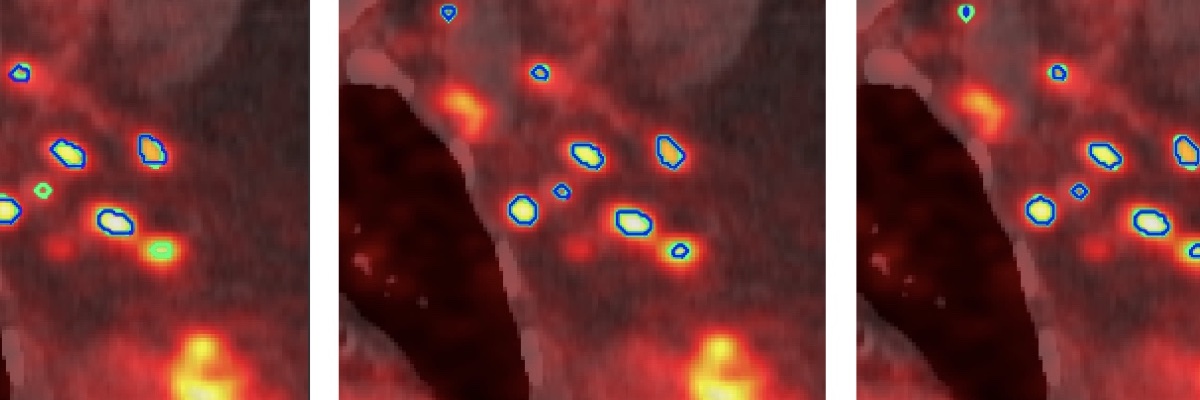

Les champs d'expertise numérique de l'équipe reposent sur les champs suivants : intelligence artificielle, image, analyse exploratoire de données, observabilité des données, analyse multiéchelle, morphologie mathématique, topologie discrète, filtrage spatio-fréquentiel, analyse dynamique, classification, décision, mesure de similarité, détection de changements, modélisation statistique.

Les champs d'expertise clinique de l'équipe reposent sur les modalités suivantes : imagerie par résonance magnétique (IRM), scanner (TDM), artériographie, imagerie nucléaire (TEP, TEMP), électroencéphalographie (EEG), échographie, imagerie préclinique (synchrotron). Les domaines cliniques privilégiés sont la néonatologie, la cancérologie, la neurologie, la radiologie, l'endocrinologie, l'urologie, l'histopathologie.